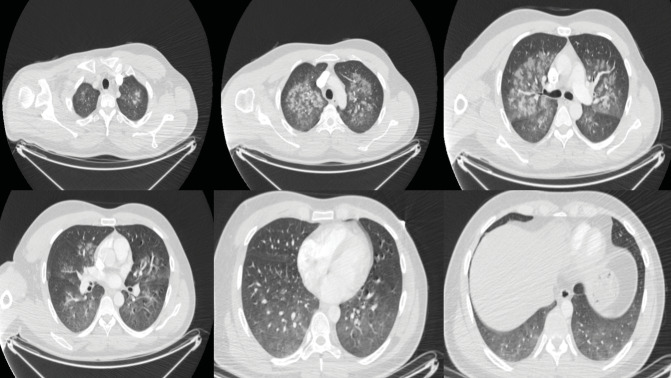

七氟醚是一种常用的吸入麻醉剂,用于诱导和维持全身麻醉。然而,它与一种罕见但严重的肺部疾病--弥漫性肺泡出血(DAH)--有关。弥漫性肺泡出血的特点是血红蛋白水平下降、弥漫性肺浸润以及伴有低氧血症的呼吸衰竭。我们介绍了一例在一次并不复杂的骨科手术中使用吸入七氟醚进行全身麻醉后出现 DAH 的健康年轻成人。值得注意的是,该患者没有其他风险因素或已知病因可能导致 DAH 的发生。

Sevoflurane is a commonly used inhalational anesthetic agent for inducing and maintaining general anesthesia. However, it has been associated with a rare but serious pulmonary condition known as diffuse alveolar hemorrhage (DAH). DAH is characterized by decreased hemoglobin levels, diffuse pulmonary infiltration, and respiratory failure with hypoxemia. We present a case of DAH in a healthy young adult who experienced this condition following general anesthesia with inhaled sevoflurane during an uncomplicated orthopedic procedure. Notably, there were no other risk factors or known causes that could account for the development of DAH in this patient.